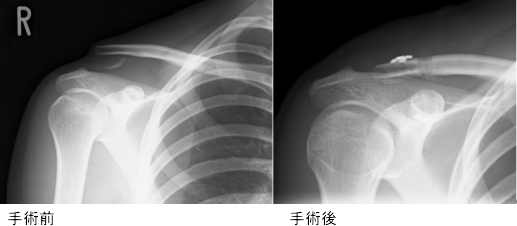

レントゲン画像

脱臼整復が維持され、柔道に復帰した方もおられます。可動域の回復に時間がかかりますが、痛みが軽快し、患者さんは喜んでおられます。